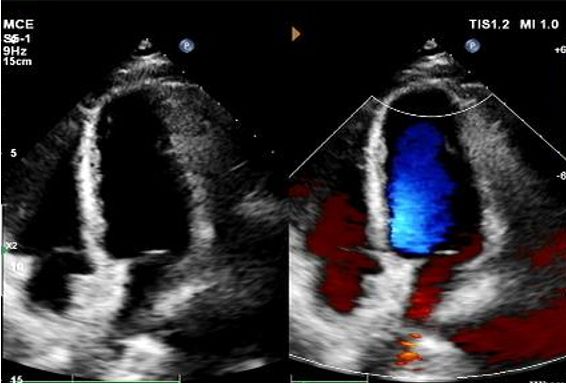

Da 1 a 9 mesi da giorno:

Nessuno shunt residuo osservato.

Riduzione graduale dell'ecogenicità del dispositivo.